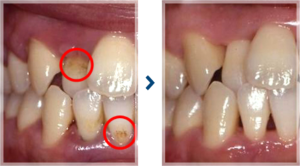

軽度歯周病の治療例

歯石除去して、歯周病治療後、歯ぐきの引き締まった状態